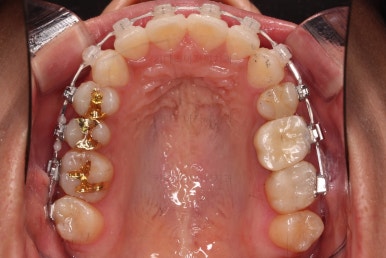

틈이 다 없어졌고, 교합도 양호합니다.

무엇보다 임플란트 없이 결손부위가 깔끔하게 채워졌고요.

매우 다행으로 사랑니도 다 있었기 때문에 마치 큰 어금니가 다 있는 것과 같은 상황이 되었습니다.

역설적이게도 손상된 큰 어금니가 없었던 부위는 작은 어금니를 발치함으로 인해 오히려 치아 갯수가 모자라 보이는 상황까지 왔네요.(어금니가 결손된 부분이 더 자연스럽게 보이는 상황)

총 치료기간도 2년 반, 30개월이 걸렸습니다.

3년 이상 봐야 되는 부산사랑니교정 치료라고 말씀 드리고 시작했음에도 예상보다 훨씬 빨리 종료 되어 매우 만족스러운 치료였습니다.

입안의 모습은 더할나위 없이 잘 개선되었고요.

상하좌우 이 뽑은 위치와 크기가 달라 이정도 중앙선은 매우 잘 맞는 상황인거고요.

임플란트도 안해도 되면서 사랑니까지 잘 사용하고 2년 반 밖에 치료기간도 안걸린 매우 좋은 치료였다고 생각되어집니다.

이상 어금니가 결손되어 있고, 돌출입이었던 환자분을 미니스크류를 이용해 사랑니까지 당겨와서 임플란트 없이 치료를 한 부산사랑니교정 치료사례였습니다.